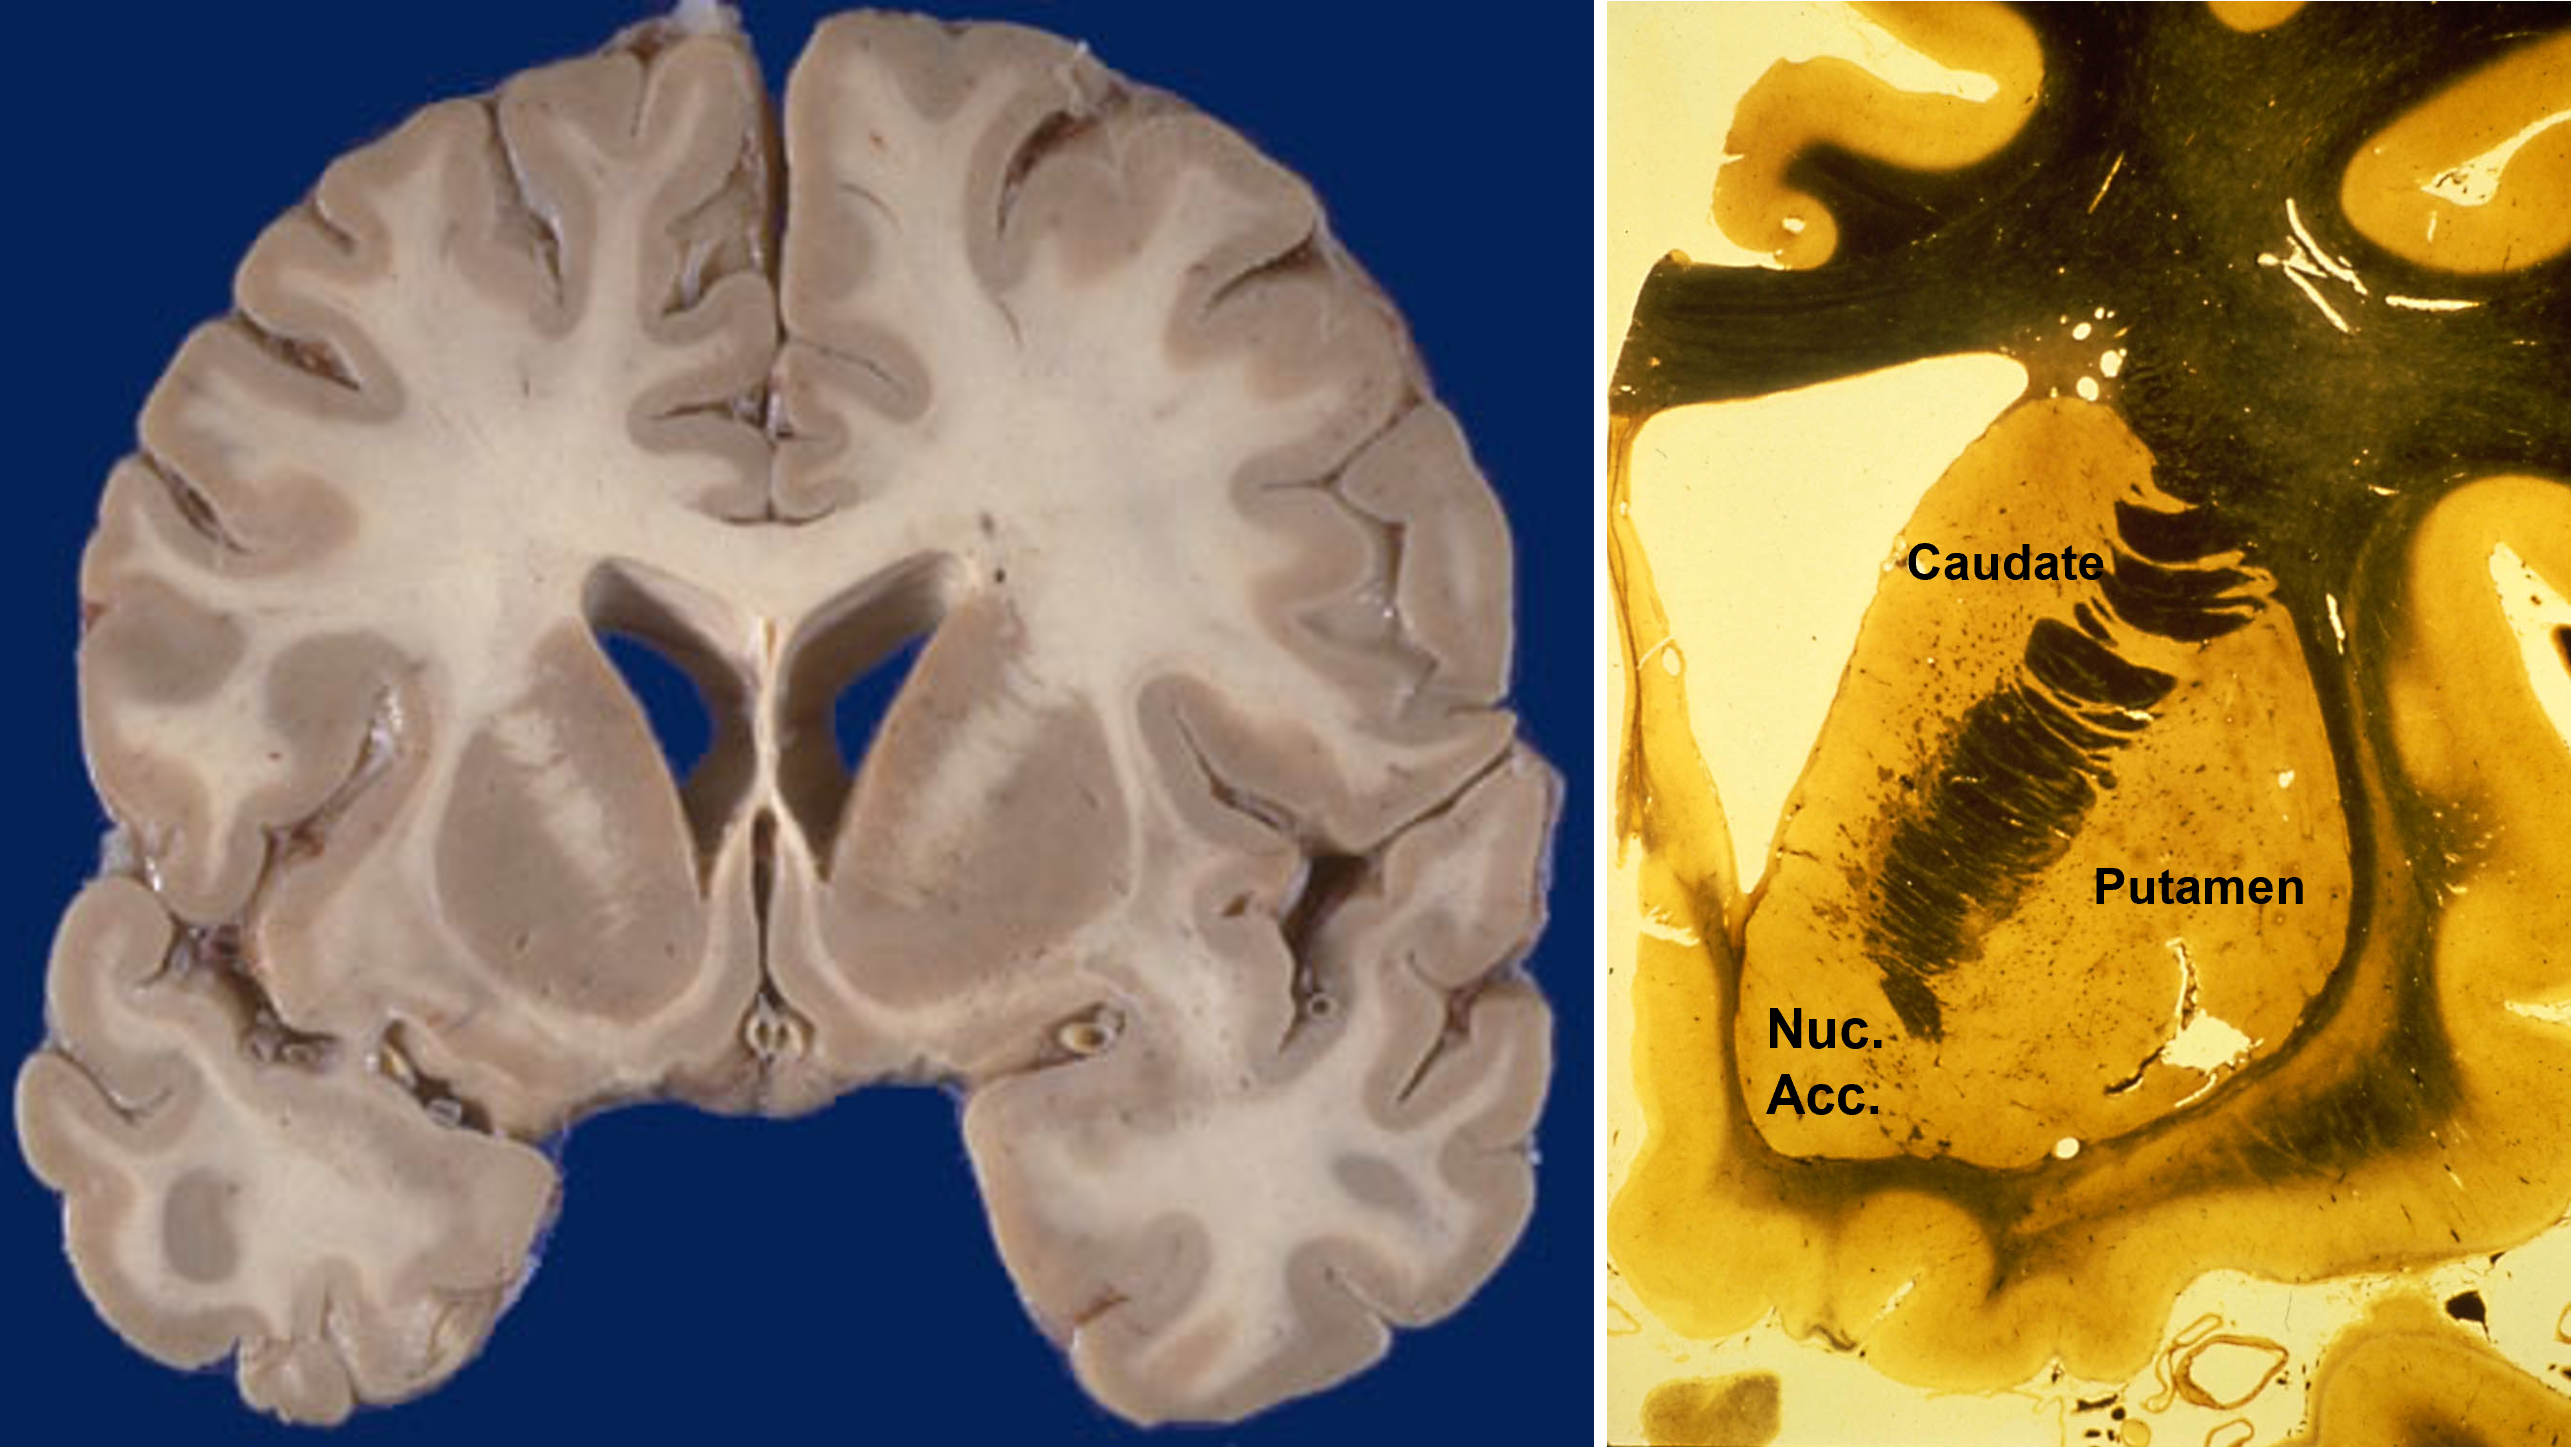

the basal ganglia have three input nuclei that receive projections from all parts of cerebral cortex

Among these three input nuclei, the caudate processes cognitive information, the putamen processes sensorimotor information, and the nucleus accumbens processes limbic information.

the caudate and putamen are cytologically identical and have similar embryological origins

The caudate, putamen, and nucleus accumbens have identical cell types and perform similar computations, but receive inputs from different cortical regions. In primates, the separation between caudate and putamen is due to fibers growing between the cortex and thalamus during embryological development. These nuclei are not separated in rats.

the caudal level of the basal ganglia look like this

includes:

caudate

ventrolateral thalamus

ventroanterior thalamus

globus pallidus

putamen

subthalamic nucleus